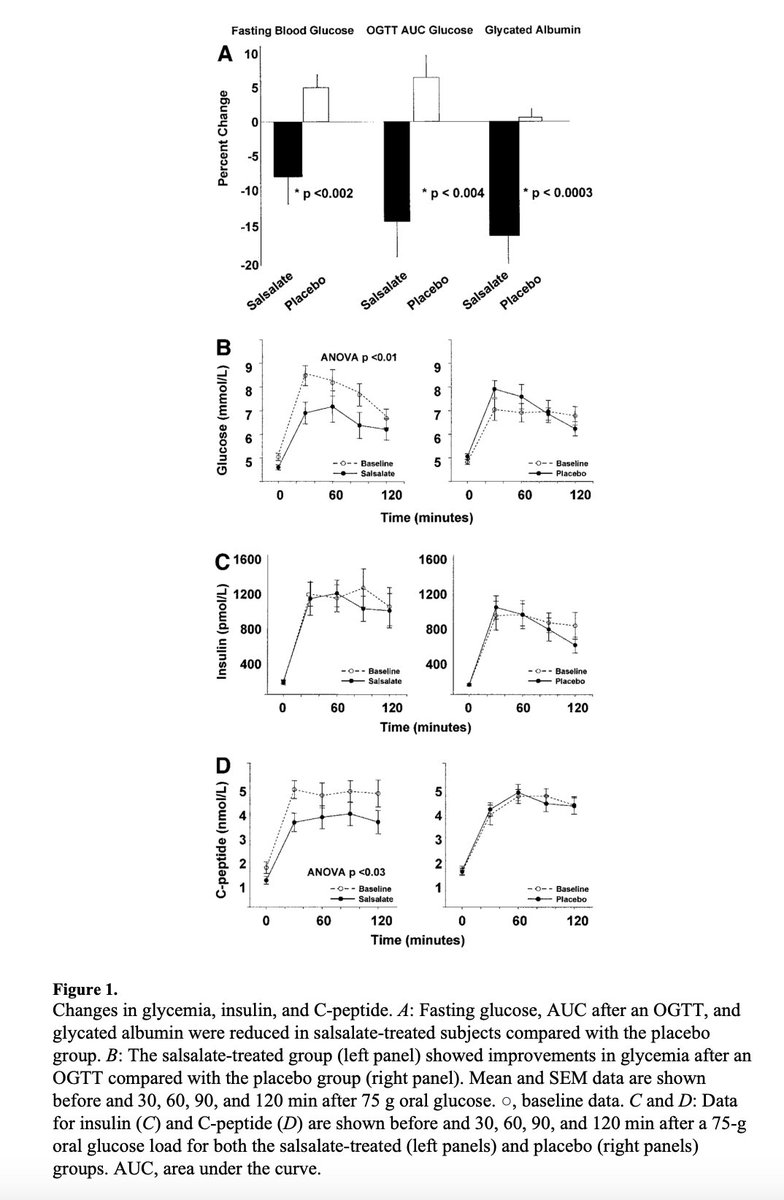

One of the KEY benefits of aspirin is its ANTI STRESS properties.

Many people report calmness and better sleep on aspirin, and this is likely a prime reason why.

Aspirin can actually lower the output of cortisol, our primary stress hormone, at baseline.

Many people report calmness and better sleep on aspirin, and this is likely a prime reason why.

Aspirin can actually lower the output of cortisol, our primary stress hormone, at baseline.

Aspirin ALSO lowers cortisol release in response to various stressors, allowing us to avoid some of the deleterious effects of excess stress in these situations.

Post exercise this can be very valuable if you’re completely drained or wired.

Post exercise this can be very valuable if you’re completely drained or wired.